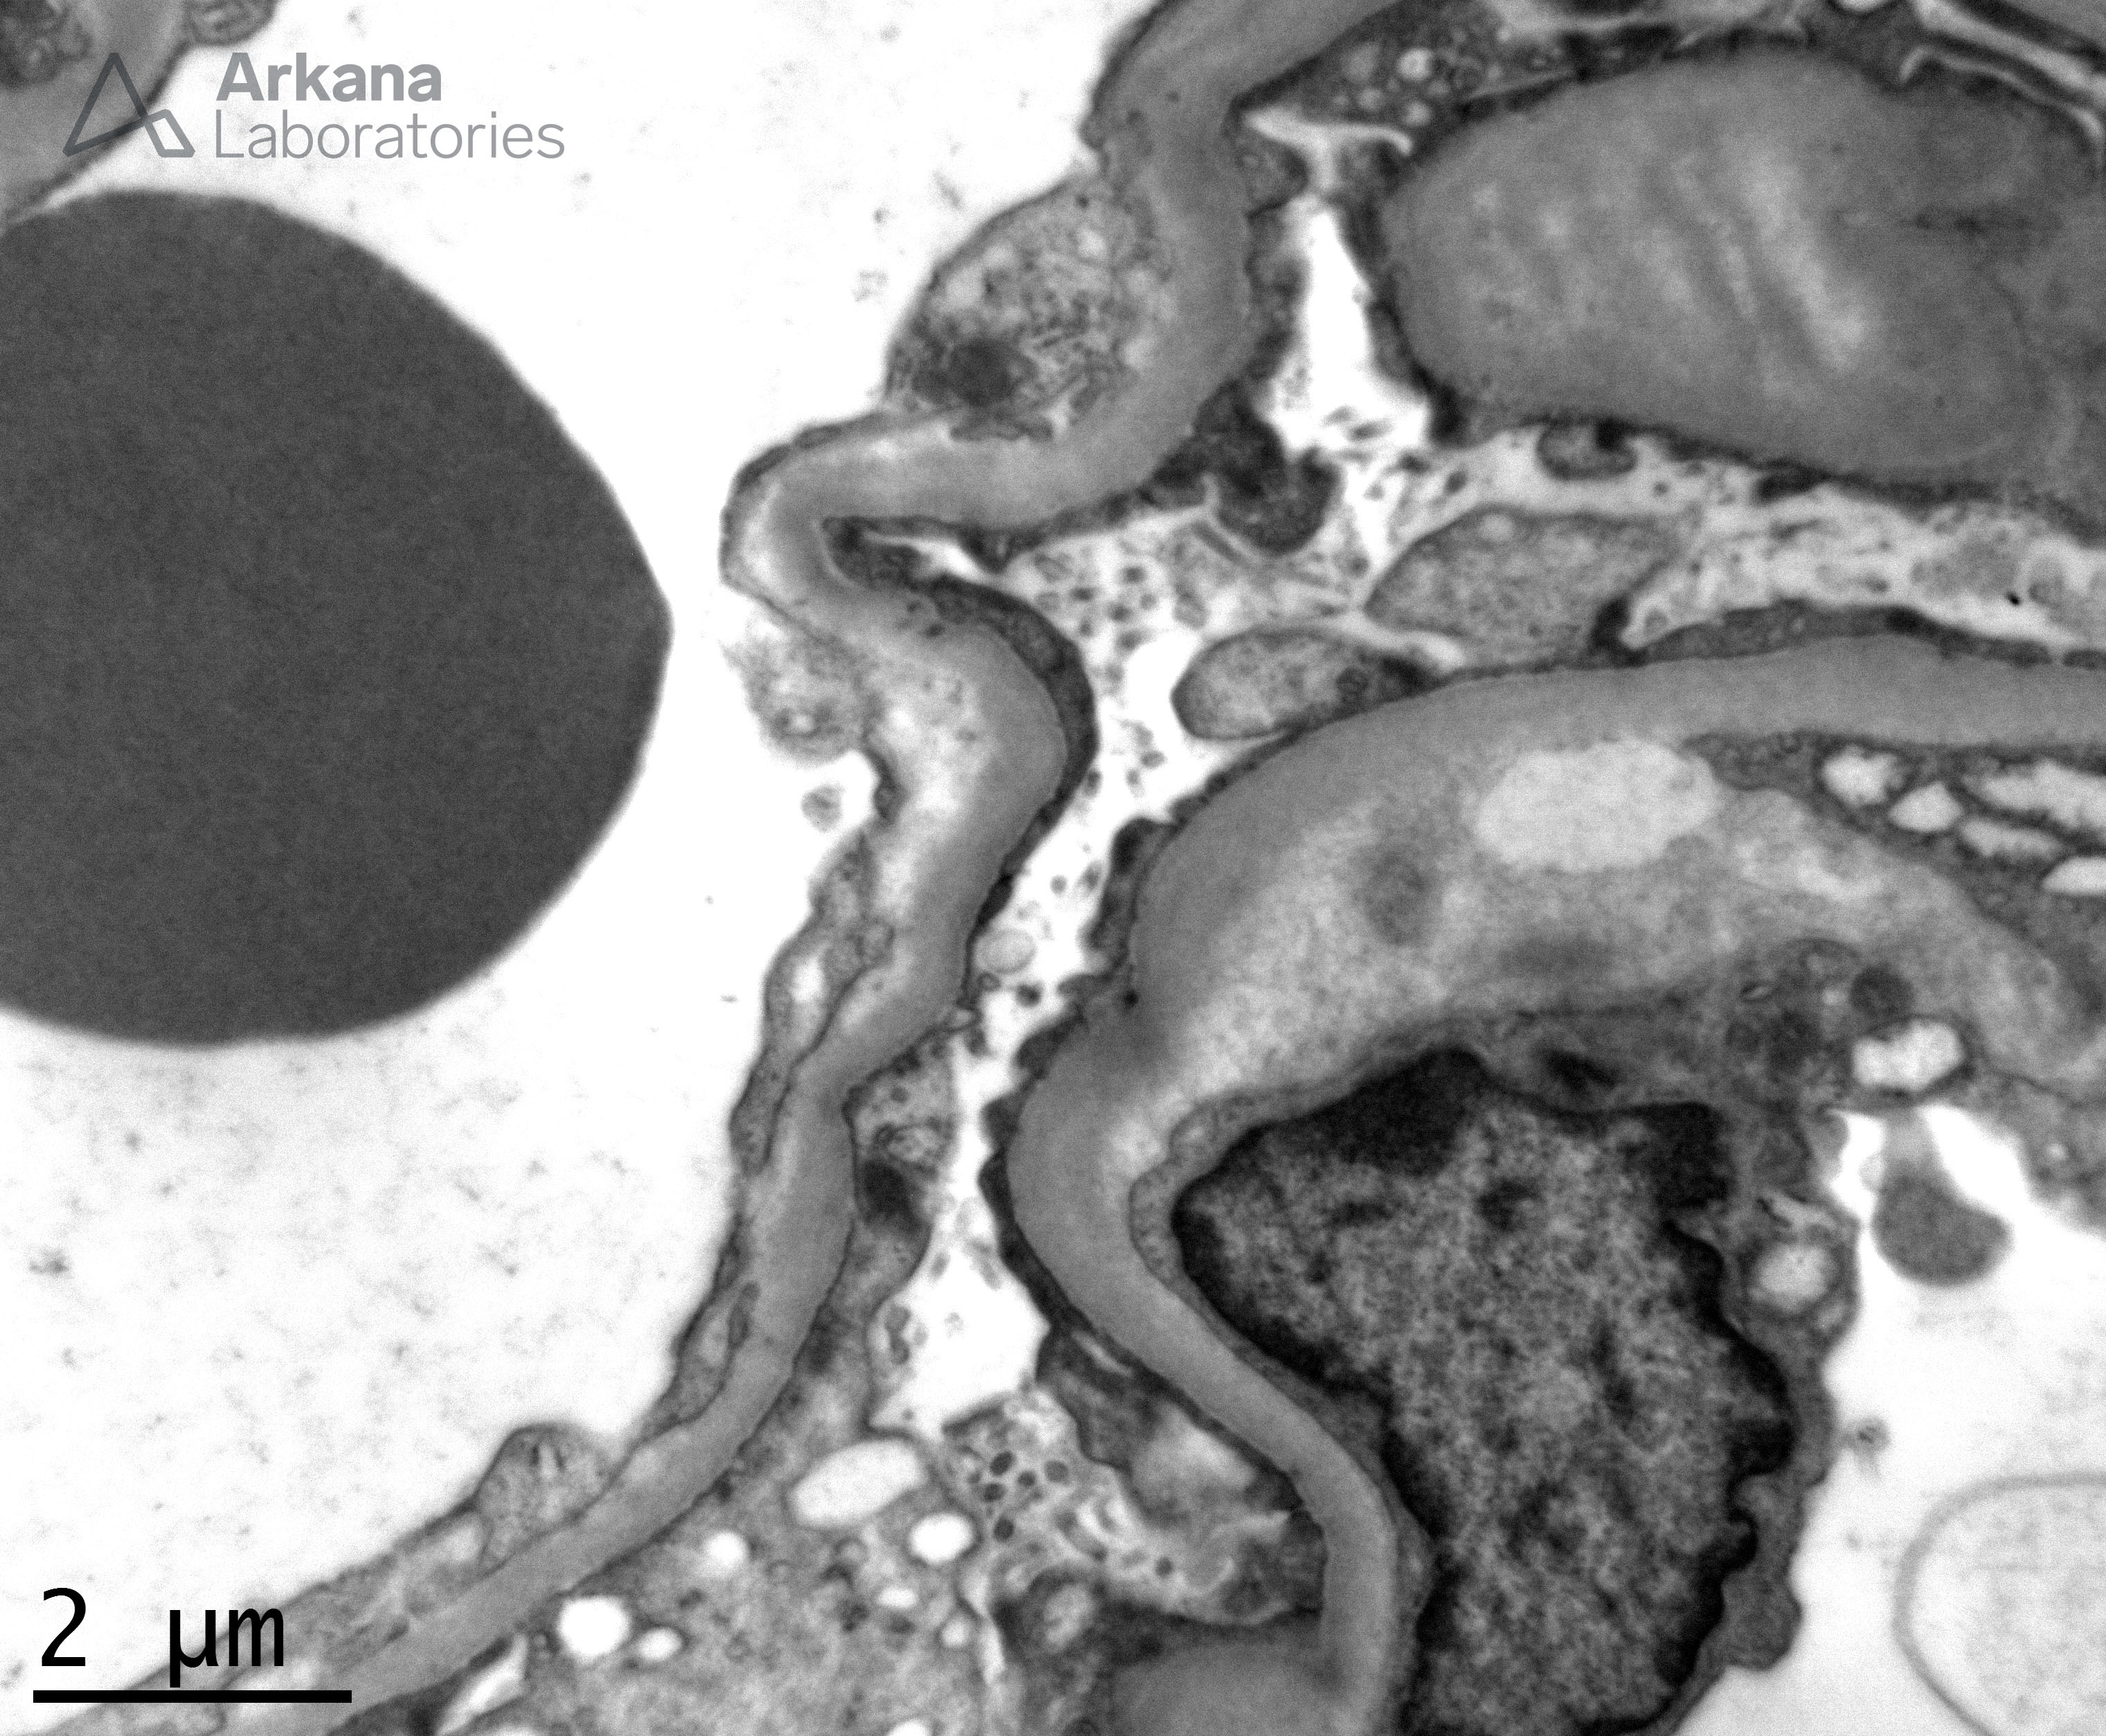

GBM with Subendothelial Electron Lucent Widening